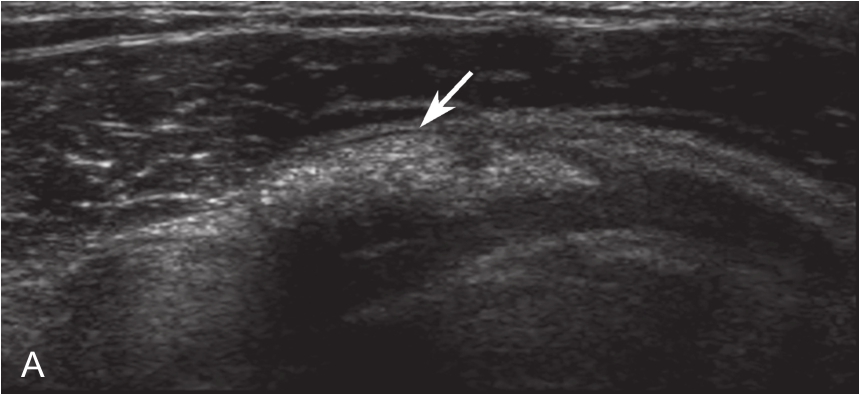

▲ 图2-2-4 超声引导下肩袖钙化性肌腱炎介入治疗超声图

短箭头:钙化灶;长箭头:穿刺针